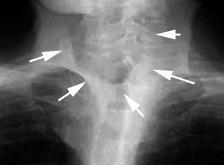

Radiografía AP en politraumatizado con enfisema subcutáneo severo.

Kumar H M,et al. Ginkgo leaf sign and subcutaneous emphysema.BMJCase Rep .2018